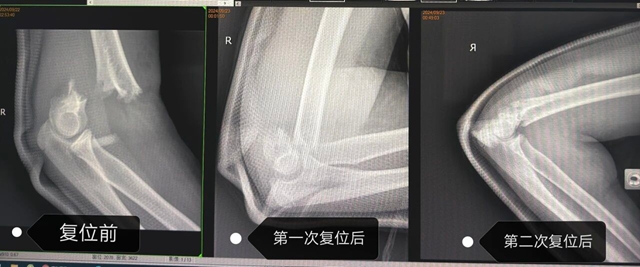

考虑到小丽伤情较重,为确保复位效果,王念武陪着孩子立即复查X片,结果显示桡骨远端骨折完全复位,但肱骨髁上骨折移位虽明显改善,但仍不够理想,还需进一步调整。看着患者越加肿胀的肢体,综合考虑,在和患者家属沟通后随即决定立即再次行正骨复位,不然后期肿胀加剧很可能就没有再次复位机会了。

王念武医生当机立断,就在影像室对肱骨髁上骨折再次行手法复位,第二次正骨结束后,小丽惊喜地告诉家长:“胳膊没那么痛了!”试着活动手指,也比之前灵活了不少,麻木也减轻了。

立即复查X片,骨折对合良好,复位成功!兴奋之余,医生和家属也松了口气,但都略显疲惫,而此时已是凌晨2点。

复位前后对比